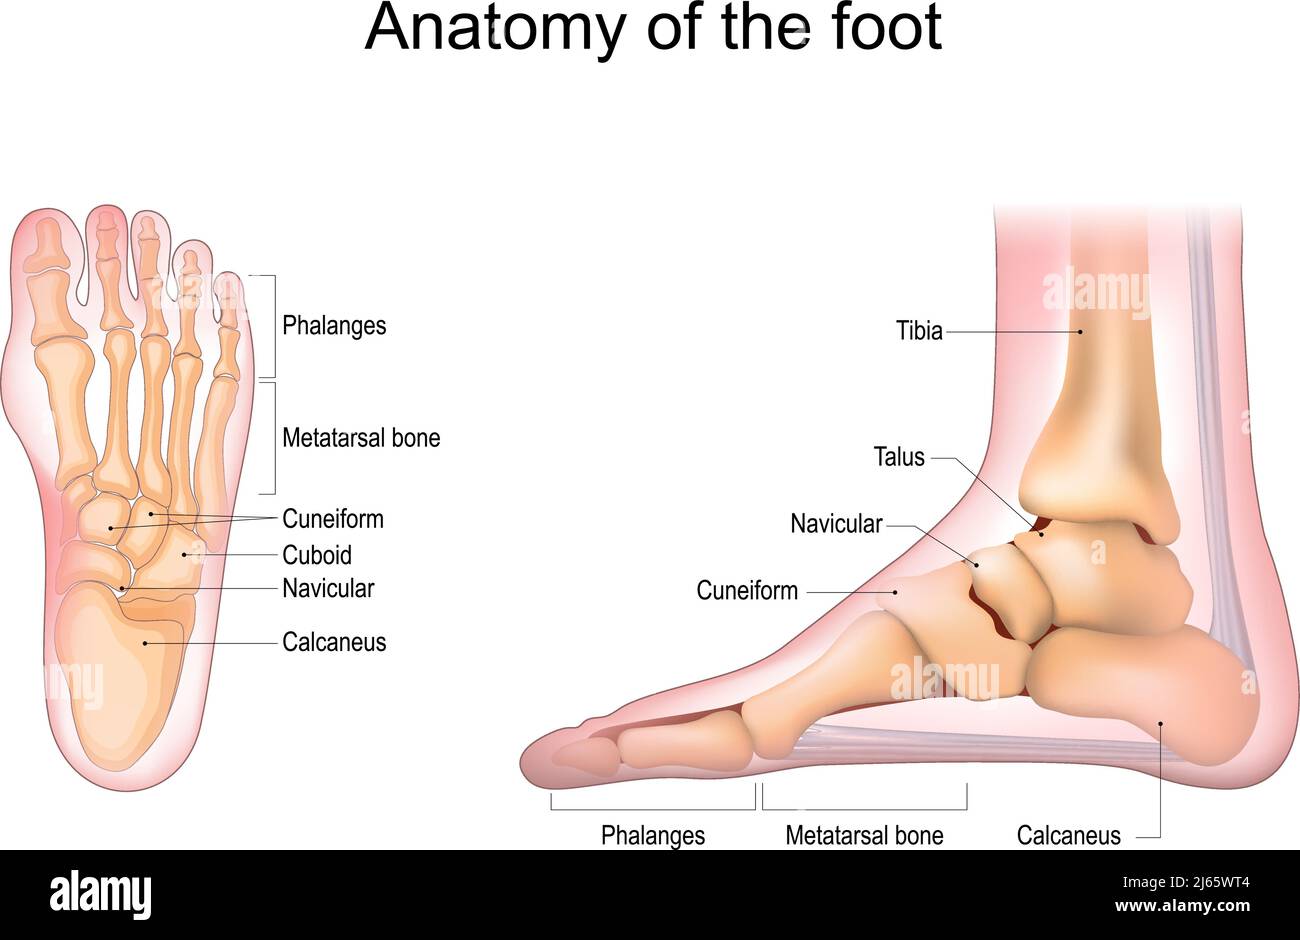

RF2J65WT4–Anatomie du pied. Pied humain avec le nom et la description de tous les os et sites. Vue de dessus et vue latérale. Arcs des pieds. Anatomie du squelette. Vecteur

RF2WNN754–Illustration médicale des principales parties des os du pied en vue antérieure, avec annotations.

RF2WWY5XN–Os du pied humain avec le nom et la description de tous les sites. Vue supérieure. Anatomie humaine. Illustration vectorielle isolée sur un fond blanc.